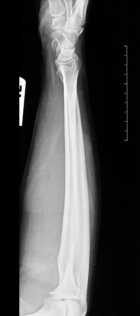

M.M. - 53 year old male with a painful right forearm mass

Zoom image: Radiological image Radiological image.